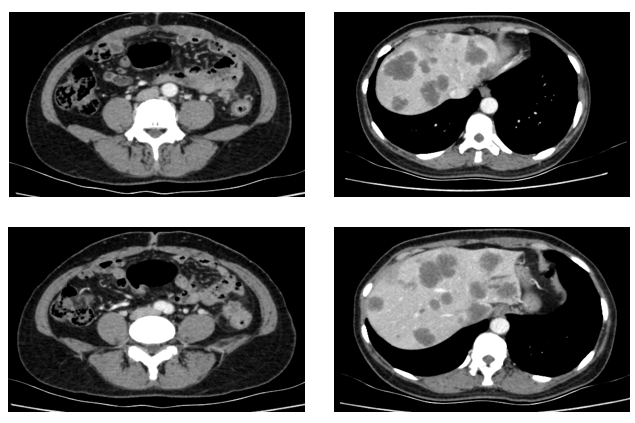

残余病灶的手术切除:2023-02-22至外院行“左半肝切除术,尾状叶切除术,肝段切除术,胆囊切除术,腹腔淋巴结清扫术,肠粘连松解术,肾周围粘连分解术,肝脏肿物射频消融,肝动脉结扎,腔静脉损伤修复术”。

再次行基因检测,结果提示:HER2扩增倍数为5.49倍

CT(2023.4.14)提示:肾上腺病变较前增大,考虑PD